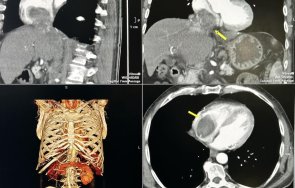

Лекари спасиха пациент с огромен тумор в черния дроб и сърцето